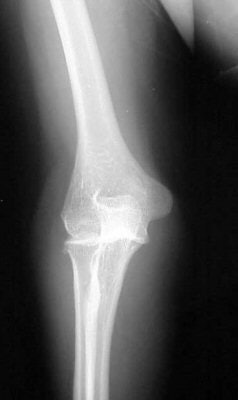

In figure 1 we have an attempted AP view of the elbow in a 10-year-old male. Because the child was unable to fully extend his arm, his body was partially oblique to the affected side, and the arm was extended as far as possible.

Upon completion of the lateral film (figure 2), which was done with the film tucked between the child's arm and his body and shot cross-table in a wheelchair, it is evident why the arm is in a fixed position. Note the subluxation of the humeral condyles from the olecranon process (arrow).